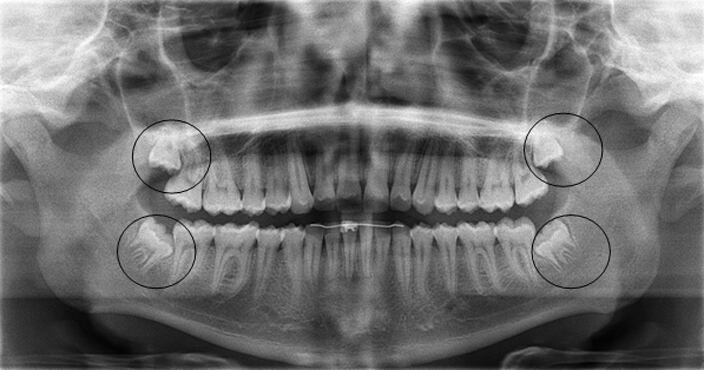

Erik Edge, un joven de 17 años de Spokane, Washington, falleció tras sufrir una complicación con la anestesia durante una cirugía rutinaria de extracción de las cordales, también conocidas como las muelas del juicio.

El procedimiento tuvo lugar en Liberty Oral and Facial Surgery, en Estados Unidos. Tras la administración de la anestesia, la garganta del joven se bloqueó, lo que impidió su respiración.

Erik era estudiante de la Escuela Preparatoria Gonzaga y había acudido al consultorio de Liberty Oral and Facial Surgery para someterse a una cirugía rutinaria de extracción de muelas del juicio. Su padre, Mark Edge, lo acompañó con la esperanza de que fuera un procedimiento rápido y sin complicaciones. Sin embargo, mientras esperaba en la sala de espera, presenció un dramático giro de los acontecimientos.